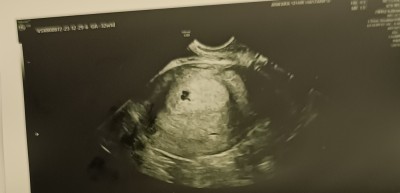

Kızlar Dün doktora gittim ilk defa Doktor muayenesine gittim ama üstten baktı göremedi Doğum Hastanesi'ne yönlendirdi Doğum Hastanesi'nin aciline gittim vajinal baktılar ve kesimin biraz düzensiz olduğunu söylediler Ama Beta değerim yüksek geldi 5900 geldi Sizce kesen bozuk mu veya düzelir mi

Gebelik haftası 5

Bebeği göremedi ama bebeği oluşturabilecek plasentayı gördüğünü söyledi zaten hastanedeki doktorlar insanı korkutmaktan başka bir şey yapmıyor hemen yatış yapmamı söyledi ve kürtaj olmam gerektiğini söyledi Tabii ki de kabul etmedim Çünkü içimde bir umut var Ve düzelebileceğine inanıyorum